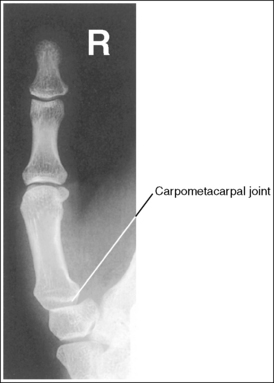

See Figures 4-12 and 4-13 and Box 4-5.

See Figures 4-16 and 4-17 and Box 4-6.

See Figure 4-22 and Box 4-8.